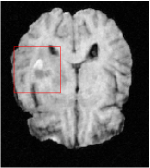

In this section, we test the generalizability of the proposed model that tests on unseen tasks. We fix the well-trained task-invariant parameter and only train for sampling ratios 15%, 25% and 35% with radio masks and sampling ratios 10%, 20%, 30% and 40% with Cartesian masks. In this experiment, we only used 100 training data for each CS ratio and apply a total of 50 epochs. The averaged evaluation values and standard deviations are listed in Table 5.4 and 5.4 for reconstructed T1 and T2 brain images respectively that proceed with radio masks, and Table 5.4 shows the qualitative performance for reconstructed T2 brain image that applied random Cartesian sampling masks. In T1 image reconstruction results, meta-learning improved 1.6921 dB in PSNR for 15% CS ratio, 1.6608 dB for 25% CS ratio, and 0.5764 dB for 35% comparing to the conventional method, which in the tendency that the level of reconstruction quality for lower CS ratios improved more than higher CS ratios. A similar trend happens in T2 reconstruction results with different sampling masks. The qualitative comparisons are illustrated in Figure 2, 4 and 5 for T1 and T2 images tested in skewed CS ratios in radio masks, and T2 images tested in Cartesian masks with regular CS ratios respectively. In the experiments that conducted with radio masks, meta-learning is superior to conventional learning especially at CS ratio 15%, one can observe that the detailed region in red boxes keeps edges and is more close to the true image, while conventional method reconstructions are hazier and lost details in some complicated tissue. The point-wise error map also indicates that Meta-learning has the ability to suppress noises.

Qualitative comparison between conventional and Meta-learning methods are shown in Figure 1 and 3, which display the reconstructed MR images of the same slice for T1 and T2 respectively, we label the zoomed-in details of HGG in the red boxes. We observe the evidence that conventional learning is more blurry and lost sharp edges, especially in lower CS ratios. From the point-wise error map, we find meta-learning has the ability to reduce noises especially in some detailed and complicated regions comparing to conventional learning.